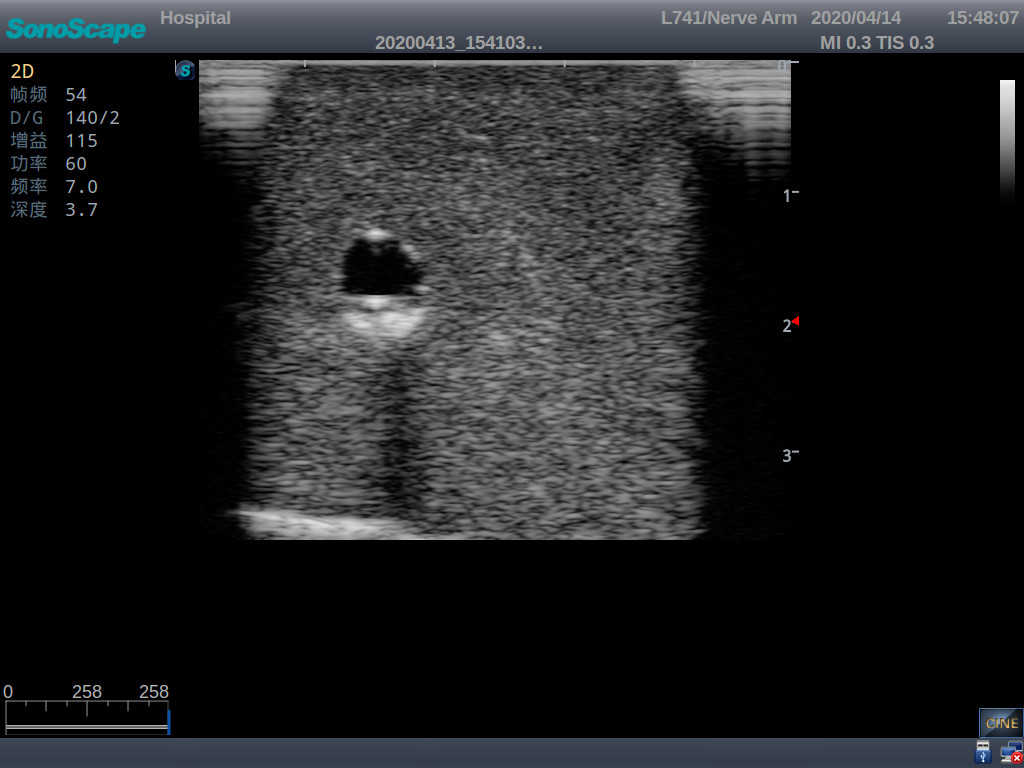

2)   It can be used by real ultrasound machines

3)   Clear and real images of the tissues and organs (basilic vein and superior vena cava)

5)   Observe the guide wire marches